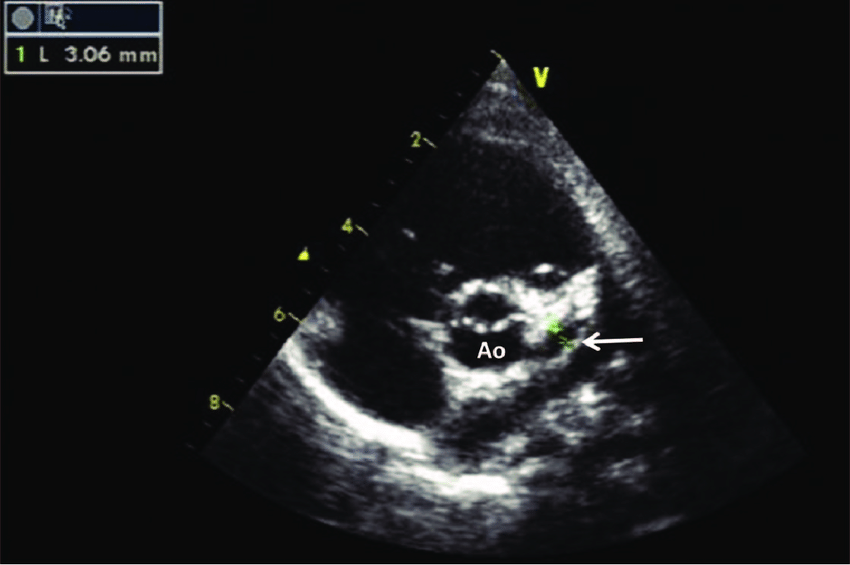

Sinuses of valsalva aneurysm

What is seen in the 2D image?

Right heart - RA or RV

Where do sinus of valsalva aneurysms most often rupture into?